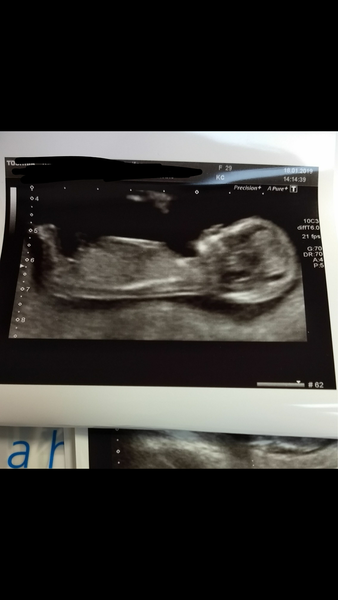

ReginaPhalange89 · 18/01/2019 14:38

Yay good news all round today girls !

My scan went really well, got tons of photos ! Measurements are putting my due date forward by a full week ! Which can't be right but I'm going with it lol. Just waiting to see the midwife now and they'll tell me my due date but think it's going to be 23rd July !

ReginaPhalange89 · 18/01/2019 14:39

💕

Lovely scans guys... @ReginaPhalange89 amazing very flat back like my little ones... what do you recon it will be... must be an expert at these things now having two children already x

Regina yaaaayyy! Lovely pic x

I honestly don't know ! I think the nub is pointing up so going by that boy,. But all the photos look so different 🙈 so really no clue . And the skull looks round in some and more square in others so honestly can't go by either nub or skull lol.

My guts saying boy just because I've been feeling different to the last 2

On another note, I asked the sonographer what she thought of the nub theory and she said she reckons it's nonsense because it can look different in each shot . She did show me between the legs and said "something there ? Hmm maybe. But it's so tiny to be sure".... So who knows !